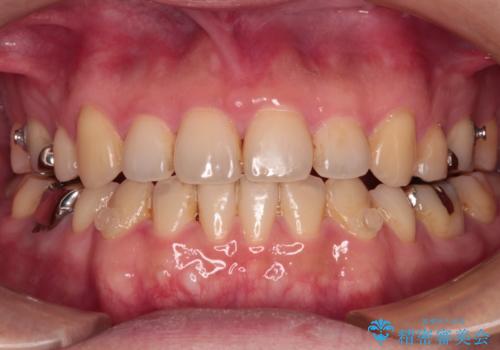

- 抜歯矯正の後戻りを気にして来院された患者様です。

舌の突出癖によるオープンバイトになり、前歯の叢生が後戻りしていました。

舌のトレーニングを行いながら、インビザラインを用いて矯正治療を行うこととしました。

インビザラインの特性を活用して奥歯の咬み合わせを圧下させることで、前歯のオープンバイトを改善さえることができました。